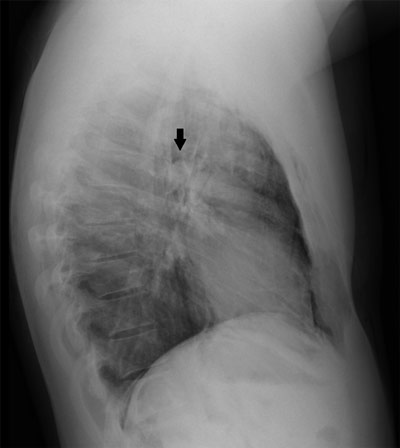

Figure B

Lateral chest radiograph showing a well-defined lucency surrounding the right pulmonary artery, also known as the ring around the artery sign (solid black arrow).